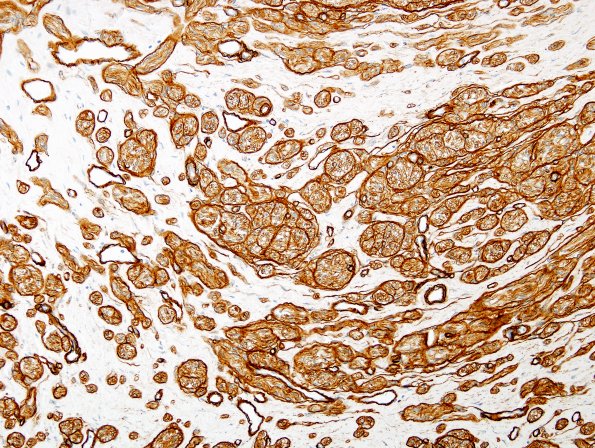

9C3 Neuroma, traumatic (Case 9) Coll IV 2

Higher magnification of mini-fascicles. (Coll IV IHC)